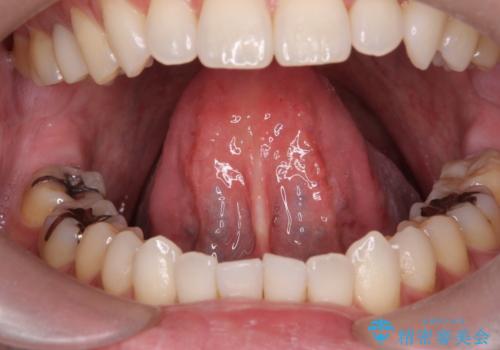

[ 舌小帯の形成 ] 滑舌の改善をしたい

担当医 大元洋佑

![[ 舌小帯の形成 ] 滑舌の改善をしたいの症例 治療前](https://seimitsushinbi.jp/wp/wp-content/uploads/2022/09/459b5062738498b637cd13998f29068e-500x350.jpg?v=1662343519)

![[ 舌小帯の形成 ] 滑舌の改善をしたいの症例 治療後](https://seimitsushinbi.jp/wp/wp-content/uploads/2022/09/2f7669bb326f4f515756a383a61feb88-500x350.jpg?v=1662343538)